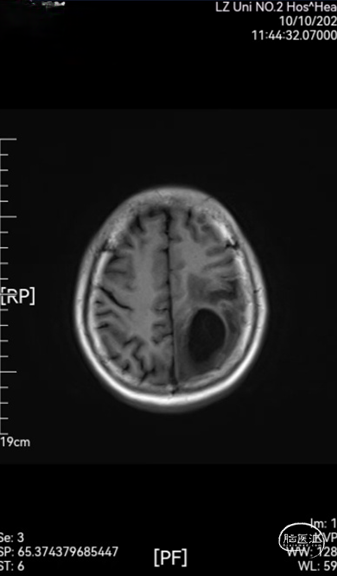

➤ 骨瓣固定:使用3个CRANIAL LOOPTM PEEK颅骨固定器进行骨瓣固定并使用2个CRANIAL COVERTM 颅骨孔盖进行铣刀钻孔封堵,之后回置骨瓣。

图2:CRANIAL LOOPTM PEEK颅骨固定器及CRANIAL COVERTM颅骨孔盖联合应用

CRANIAL LOOPTM PEEK颅骨固定器为颅骨骨瓣固定产品,CRANIAL COVERTM颅骨孔盖仅适用封堵开颅钻孔,不能用于颅骨骨瓣固定。但是,对于开颅手术的患者,两者可以搭配联合使用(如下图)。